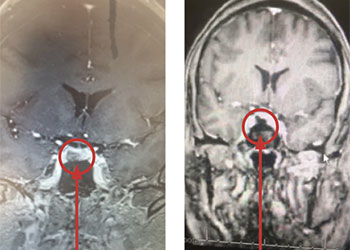

The subararachnoid hemorrhage was focused primarily within the spinal axis of the cervical thoracic and lumbar spine with secondary extension into the brain. A suspicious focal hematoma or mass was observed within the left T4-T5 region with local mass effect representing an intradural extra medullary abnormality with secondary compression of the cord and central myelopathic T2 signal abnormality (Figure 2. A,B,C,D).

Figure 2: A) T1 B) C+ T1 C) STIR D) FS C+ T1 demonstrate focal hemorrhage, contrast enhancement, mass effect, and myelopathic cord signal at T4 (arrows)